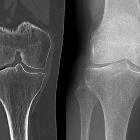

Vakuumphänomen im Kniegelenk

Vakuumphänomen

im Kniegelenk nach Trauma, jedoch unklar ob schon vorbestehend. Das intraartikuläre Gas liegt der subchondralen Lamelle der Tibia unmittelbar auf, sodass hier von einem Knorpelschaden auszugehen ist.